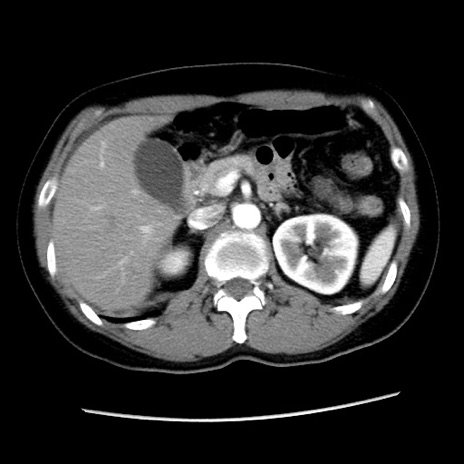

矢状断像

【症例】 50歳代女性

【主訴】 腹痛

【現病歴】前日生レバーを食べた。今朝に排便あり。 昼前に突然発症の腹痛を生じ、当院救急外来を受診した。

【既往歴】 子宮筋腫にてで子宮全摘後

【身体所見】 意識清明、腹部:平坦、軟、下腹部やや左を中心に圧痛・反跳痛あり、筋性防御あり

【データ】WBC 7800、CRP 0.07